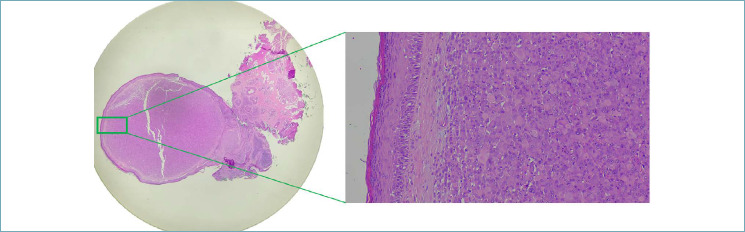

Abstract Image